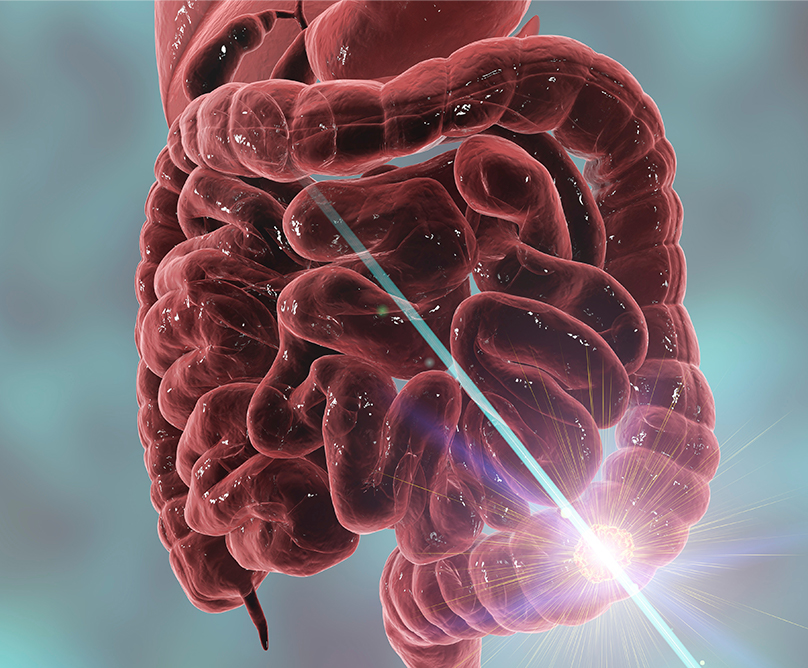

Ο καρκίνος του παχέος εντέρου και του ορθού αποτελεί την τρίτη συχνότερη κακοήθεια παγκοσμίως, με περισσότερους από 750.000 ανθρώπους κάθε χρόνο να διαγιγνώσκονται με τη συγκεκριμένη μορφή καρκίνου. Το ευχάριστο είναι πως τα ποσοστά ίασης είναι υψηλά, εφόσον το συγκεκριμένο νεόπλασμα έχει βρεθεί σε αρχικά στάδια. Από την άλλη πλευρά, δυστυχώς, παρατηρείται πως τα τελευταία χρόνια, ο καρκίνος του ορθού εμφανίζεται όλο και περισσότερο σε μικρότερες ηλικίες σε σχέση με το παρελθόν.

Η επέμβαση που γίνεται όταν κριθεί εξαιρέσιμος ο καρκίνος του ορθού είναι η χαμηλή πρόσθια εκτομή, δηλαδή η αφαίρεση του πάσχοντος τμήματος του ορθού μαζί με ολόκληρο το περιορθικό λίπος με τους λεμφαδένες και μετά η αποκατάσταση της συνέχειας του πεπτικού σωλήνα, η επανένωση του εντέρου και η αναστόμωσή του.

Οι ελάχιστα επεμβατικές τεχνικές έχουν δείξει σημαντικά οφέλη στη θεραπεία του καρκίνου του παχέος εντέρου. Ωστόσο, η χειρουργική του ορθού είναι τεχνικά πιο απαιτητική με δυσκολότερη καμπύλη μάθησης. Η διορθική προσέγγιση στην εκτομή του μεσοορθού εισήχθη για να συμπληρώσει τη συμβατική χειρουργική, έτσι ώστε να μπορούν να ξεπεραστούν οι όποιες τεχνικές δυσκολίες που σχετίζονται με την ανατομία του άπω (περιφερικού) ορθού.